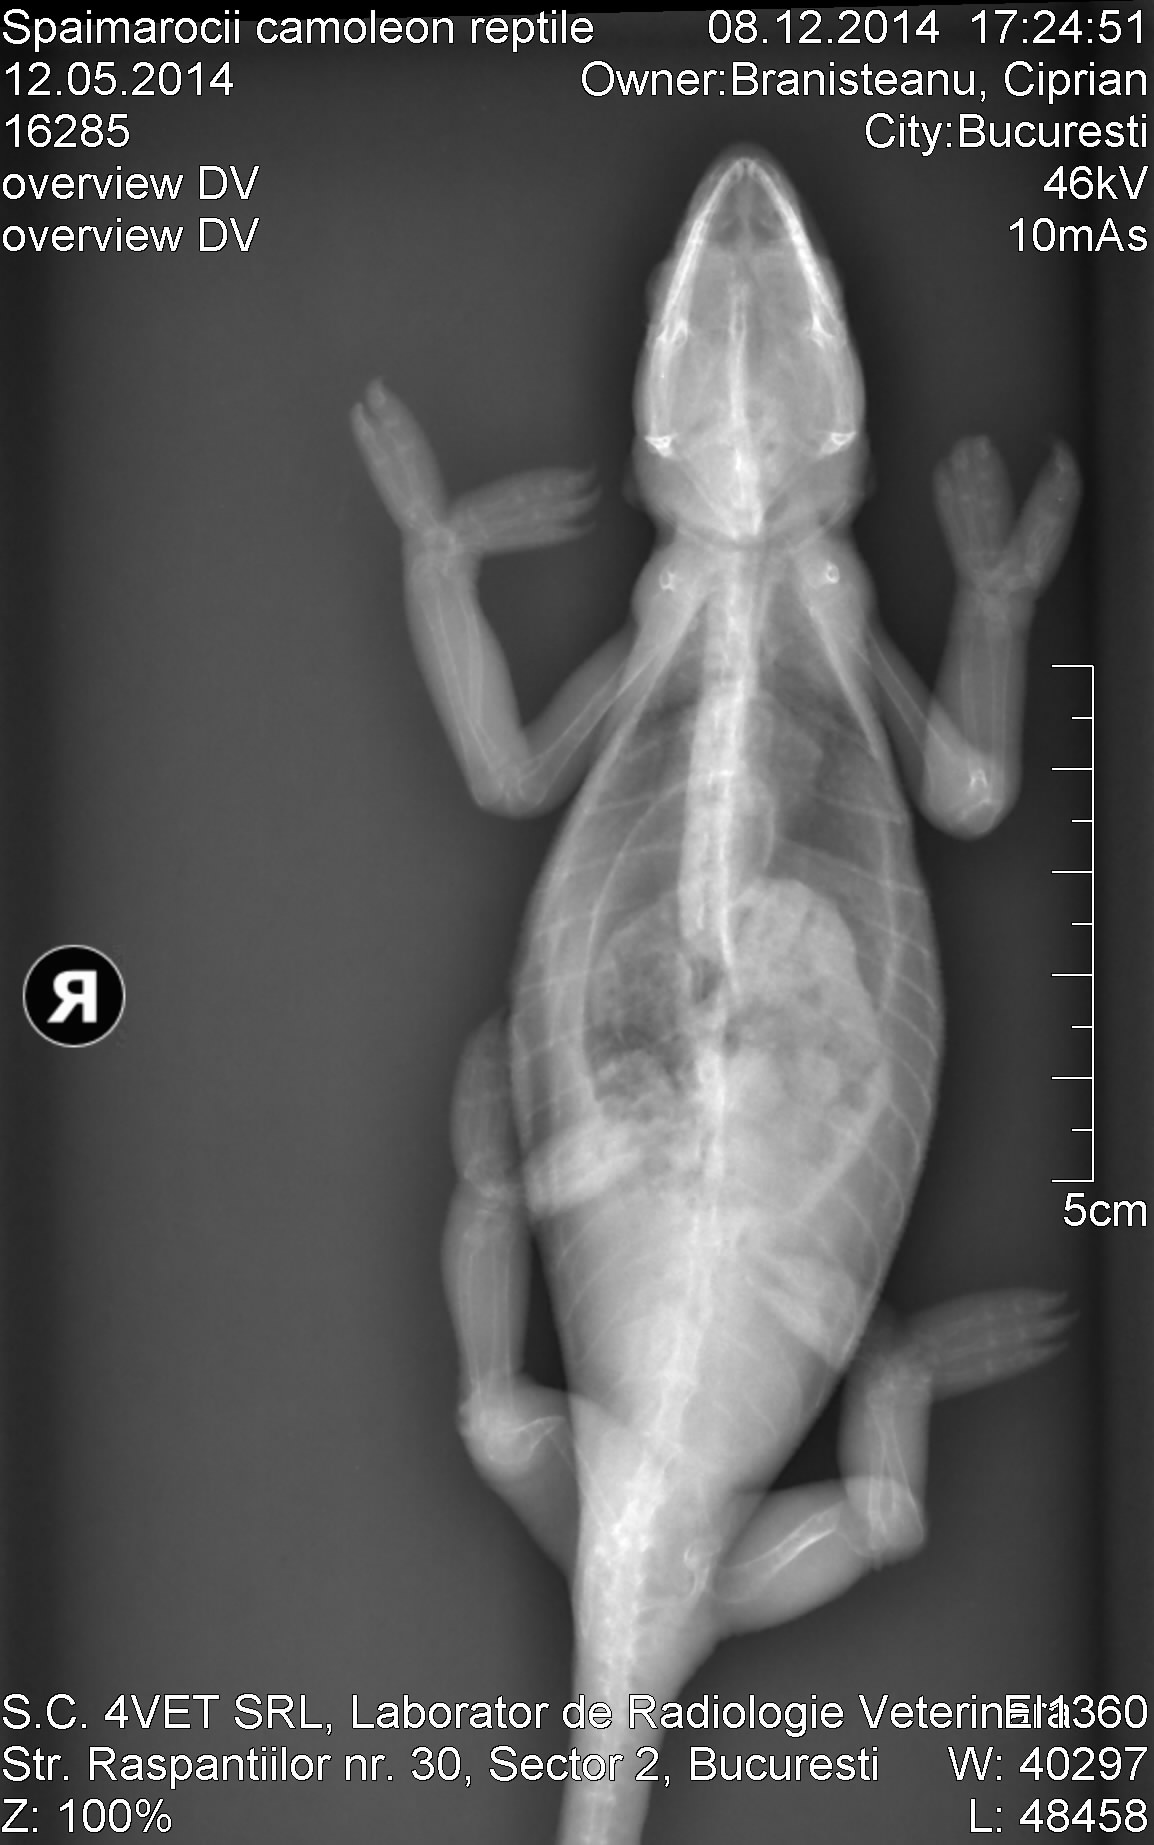

I was with my chameleon to the vet today, he made hem a radiograpy that I attach here. The vet told me the methabolic problem is mostly from missing radiation of the sun in tha cage. Looks like the chameleon have a lot of fractures. I want to take care of hem and make hem well and do whatever it takes for that, I will post info pics here regularity, help for this is very much apreciated.

The vet did some calcium injections to the fracture bone zones, give me some calcium pills that are used to the cats, and told me I should put one pill everyday inside the circket or worm before he will eat it. Then I should come back in 10 days to make hem another injections. What do you think about?

Poor little thing. You can see the fractures in the xrays. Calcium injections are good. Please take him back in ten days as recommended by the vet.

Do you have a light that emits UVB (ultraviolet light)? You should have two different kind of lights - one for heat only (basking) and a UVB light to mimic the sun. This is help your chameleon produce Vitamin D (we call it D3), which is produced naturally by the body and is required to absorb calcium. Calcium without D3 is not going to fix your chameleon, but you have to be careful not to overdose on D3. You need a UVB light immediately; chameleons cannot live without one.

I was looking at the Xray and I saw so many fractures, in one place a bone was snapped at a 90 degree angle (back left leg, what would be the femur in humans not sure if it's the same for chams), is it even possible for this girl to recover and live a healthy life?